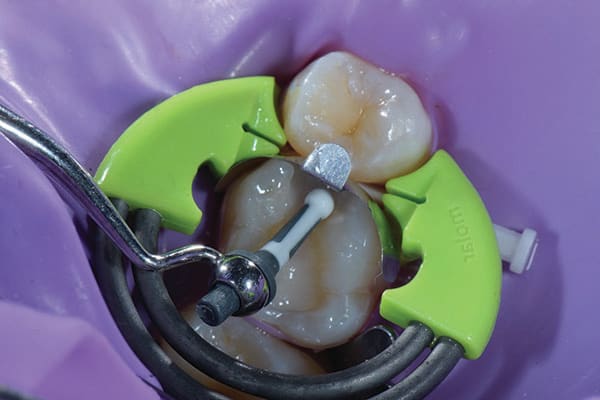

The development of the proximal surface of a Class II composite restoration is critical to its function and longevity. The location, shape, and strength of the proximal contact can affect tooth position, masticatory efficiency, food impaction, and the ease of maintaining oral hygiene.5 When delivering Class II restorations, the matrix system selected can affect the predictability and consistency of the development of properly contoured proximal surfaces and contacts. It can also affect the protection provided from fluid contamination by helping to completely seal off the preparation. The matrix system used in this case (DualForce™ Sectional Matrix System, Clinician's Choice) was selected because it provides robust separation forces and the flexibility to be used in most Class II composite scenarios (Figure 5). The matrix bands (DualForce Ultra-Wrap™ Matrix Bands, Clinician's Choice) are pre-contoured, which results in a natural proximal contact position and helps in guiding the development of the marginal ridge. Once placed, the apron of the matrix band rests gently in the gingival sulcus, well below the gingival margin. The wedges (DualForce Active-Wedges™, Clinician's Choice) are contoured in two dimensions, so the leading edge first collapses then re-expands once beyond the contact area. The separation force created by this action allows it to completely seal the gingival margin with the matrix band with an equal amount of pressure both buccally and lingually.